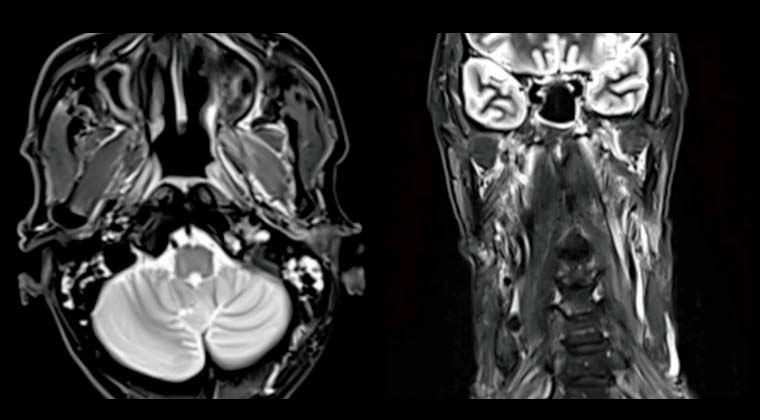

Злокачественное новообразование носоглотки (неороговевающий недифференцированный рак носоглотки)

Симптомы: дискомфорт в области шеи, преимущественно боль

Назначенная доза: PGTVnx 70,29 Гр/2,13 Гр/33 фракций, PGTVnd 67,98 Гр/2,06 Гр/33 фракций, PTV1 62,04 Гр/1,88 Гр/33 фракций, PTV2 54,12 Гр/1,64 Гр/33 фракций

Через восемь месяцев после лечения контрольная МРТ показала уменьшение опухоли носоглотки и лимфатических узлов с положительным диагнозом, регресс утолщения слизистой носоглотки.

До лечения:

После лечения: